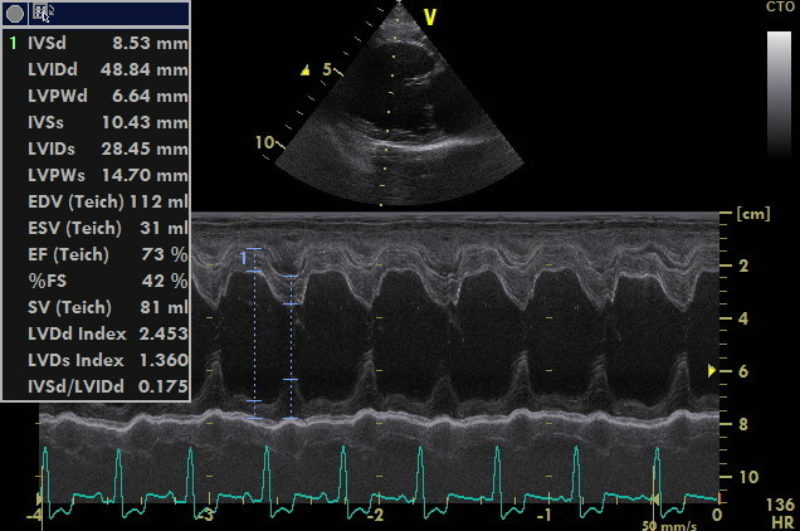

Durch die Herzultraschalluntersuchung konnte dann leider der Verdacht auf eine deutlich weiter fortgeschrittene Herzerkrankung bestätigt werden. Neben einer hochgradigen Vergrößerung der linken Herzhälfte durch die Klappeninsuffizienz ließ sich außerdem ein moderat erhöhter Druck in den Lungenarterien feststellen. Dies nennt man Pulmonale Hypertension oder Lungenhochdruck. Für eine solche Erhöhung des Blutdruckes im Lungenkreislauf gibt es unterschiedliche Ursachen. Eine davon ist ein bestehendes Lungenödem durch ein Linksherzversagen, wie es bei Alf nun offensichtlich der Fall war. Da die Diagnose nun „dekompensierte Mitralklappenendokardiose“ - oder nach der CHIEF - Klassifizierung Stadium C2 * - lautete, verordnete ich dem kleinen Hund zusätzlich zwei weitere Medikamente zur dauerhaften Herztherapie (eines zur Entwässerung und das andere zur Entlastung des Herzens durch Weitstellung der Arterien und zur Unterstützung der Pumpfunktion des Herzmuskels). Die am Morgen im Wald aufgetretene „Synkope“ ließ sich also eindeutig durch die fortgeschritten Herzerkrankung erklären.